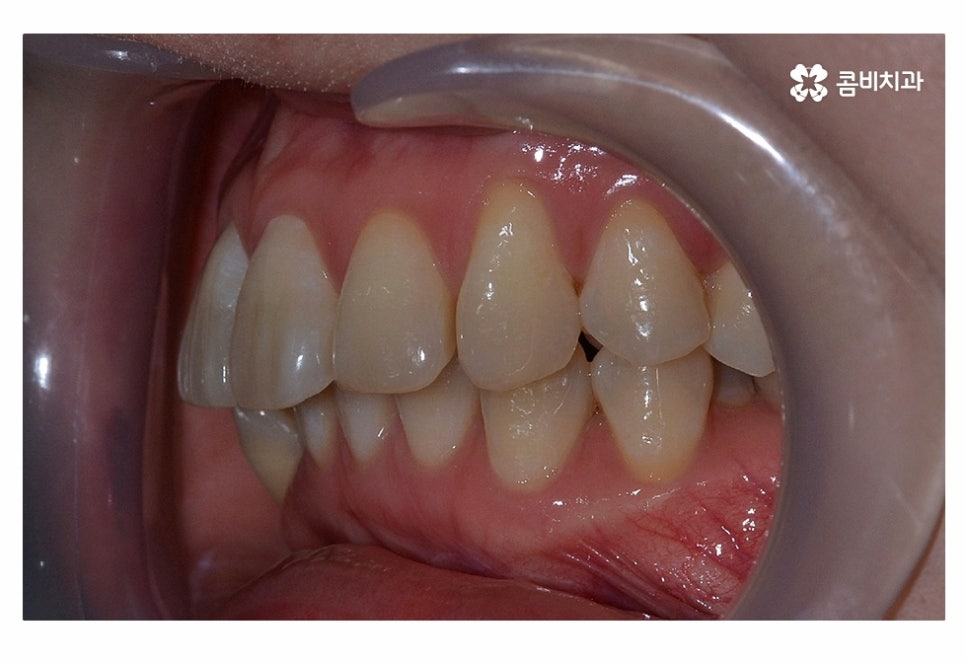

오늘 보실 교정 사례 역시도 윗니는 치아 설측교정으로

진행이 되고 아랫니는 일반적인 순측교정으로 진행되었으며

이러한 치아교정 방법을 콤비교정이라고 부르고 있어요.

위 사진에서 보시는 것과 같이 윗니의 경우 치아설측교정으로

진행이 되고 있기 때문에 교정 장치가 눈에 띄지 않고 있어요.